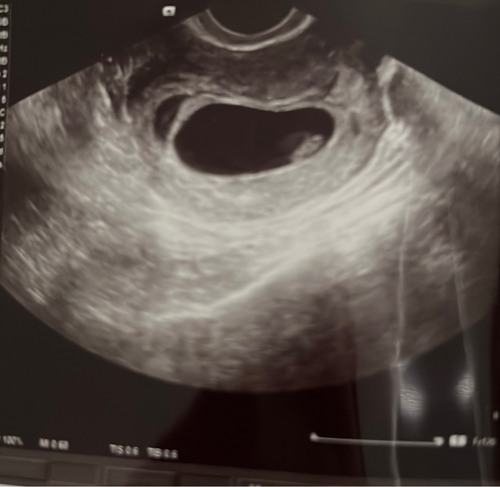

Ik had 3 weken geleden een echo met 5+5: het zijn er twee! Helaas met 6+5 was er eentje gestopt met groeien. Nu 8+5 en de ene groeit goed, de andere is bijna verdwenen.

Mijn vk zegt dat de tweede vaak verdwijnt in de vliezen van de andere als het zo klein is.

Zo’n 8 jaar terug was ik ook zwanger van een tweeling, maar toen hebben ze het allebei niet gehaald. Op de echo was toen een hartje te zien en de andere was toen al gestopt. Ze deelden toen ook samen een vruchtzak en een placenta wat de kans dat het überhaupt goed zou gaan al heel klein maakte.

Twee vruchtzakjes is in dit geval dan gunstiger.